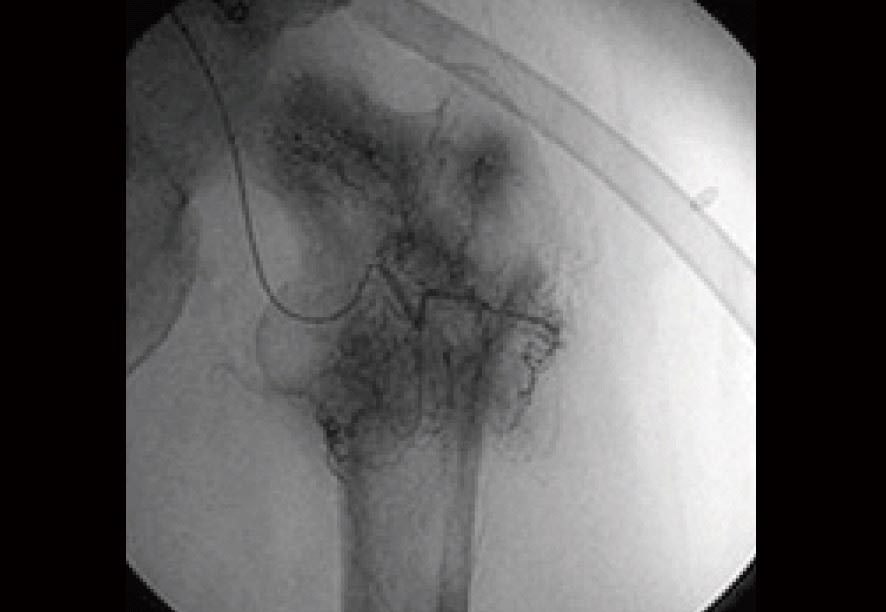

治療前のX線検査結果

参考までに、免疫治療前に実施された血管カテーテルによる骨転移の画像を見てみましょう。

この検査所見によると、左・大腿骨の周囲にはモヤモヤとしたがんの新生血管が密に認められていました(黒い部分)。

当然、この病状にいたっては歩行困難な状況であることは十分に理解できることでしょう。

この時点に受けた将来予後の見通しについては、およそ3ヶ月から半年程度であったといいます。